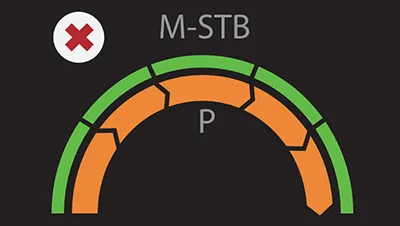

Надежный показатель контроля качества

- Индекс давления (P): качественный контроль давления зонда

- Индекс стабильности движения (m-STB): обеспечивает стабильность дыхания

- Четкая индикация с другим цветом для улучшения контроля качества во время обследования

Нарушение дыхательных движений; слишком низкое давление Prboe Состояние дыхания стабильное; Давление зонда слишком высокое

Состояние дыхания стабильное; Давление зонда слишком высокое Дыхательная система стабильна; Давление зонда соответствующее

Дыхательная система стабильна; Давление зонда соответствующееРазличные ультразвуковые решения